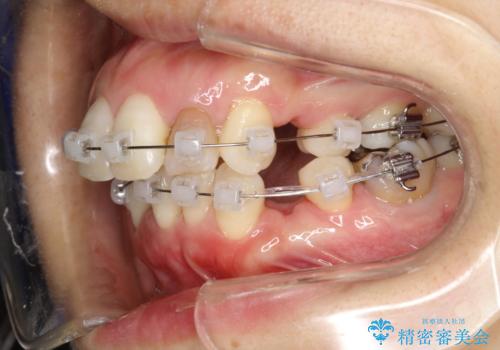

- 矯正装置

- クリアブラケット

ワイヤー矯正にて治療しました。